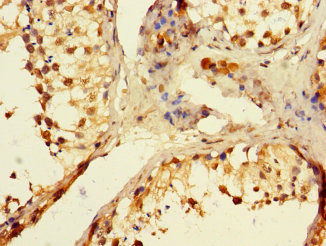

ApplicationELISA, WB, IHC; Recommended dilution: WB:1:1000-1:5000, IHC:1:20-1:200